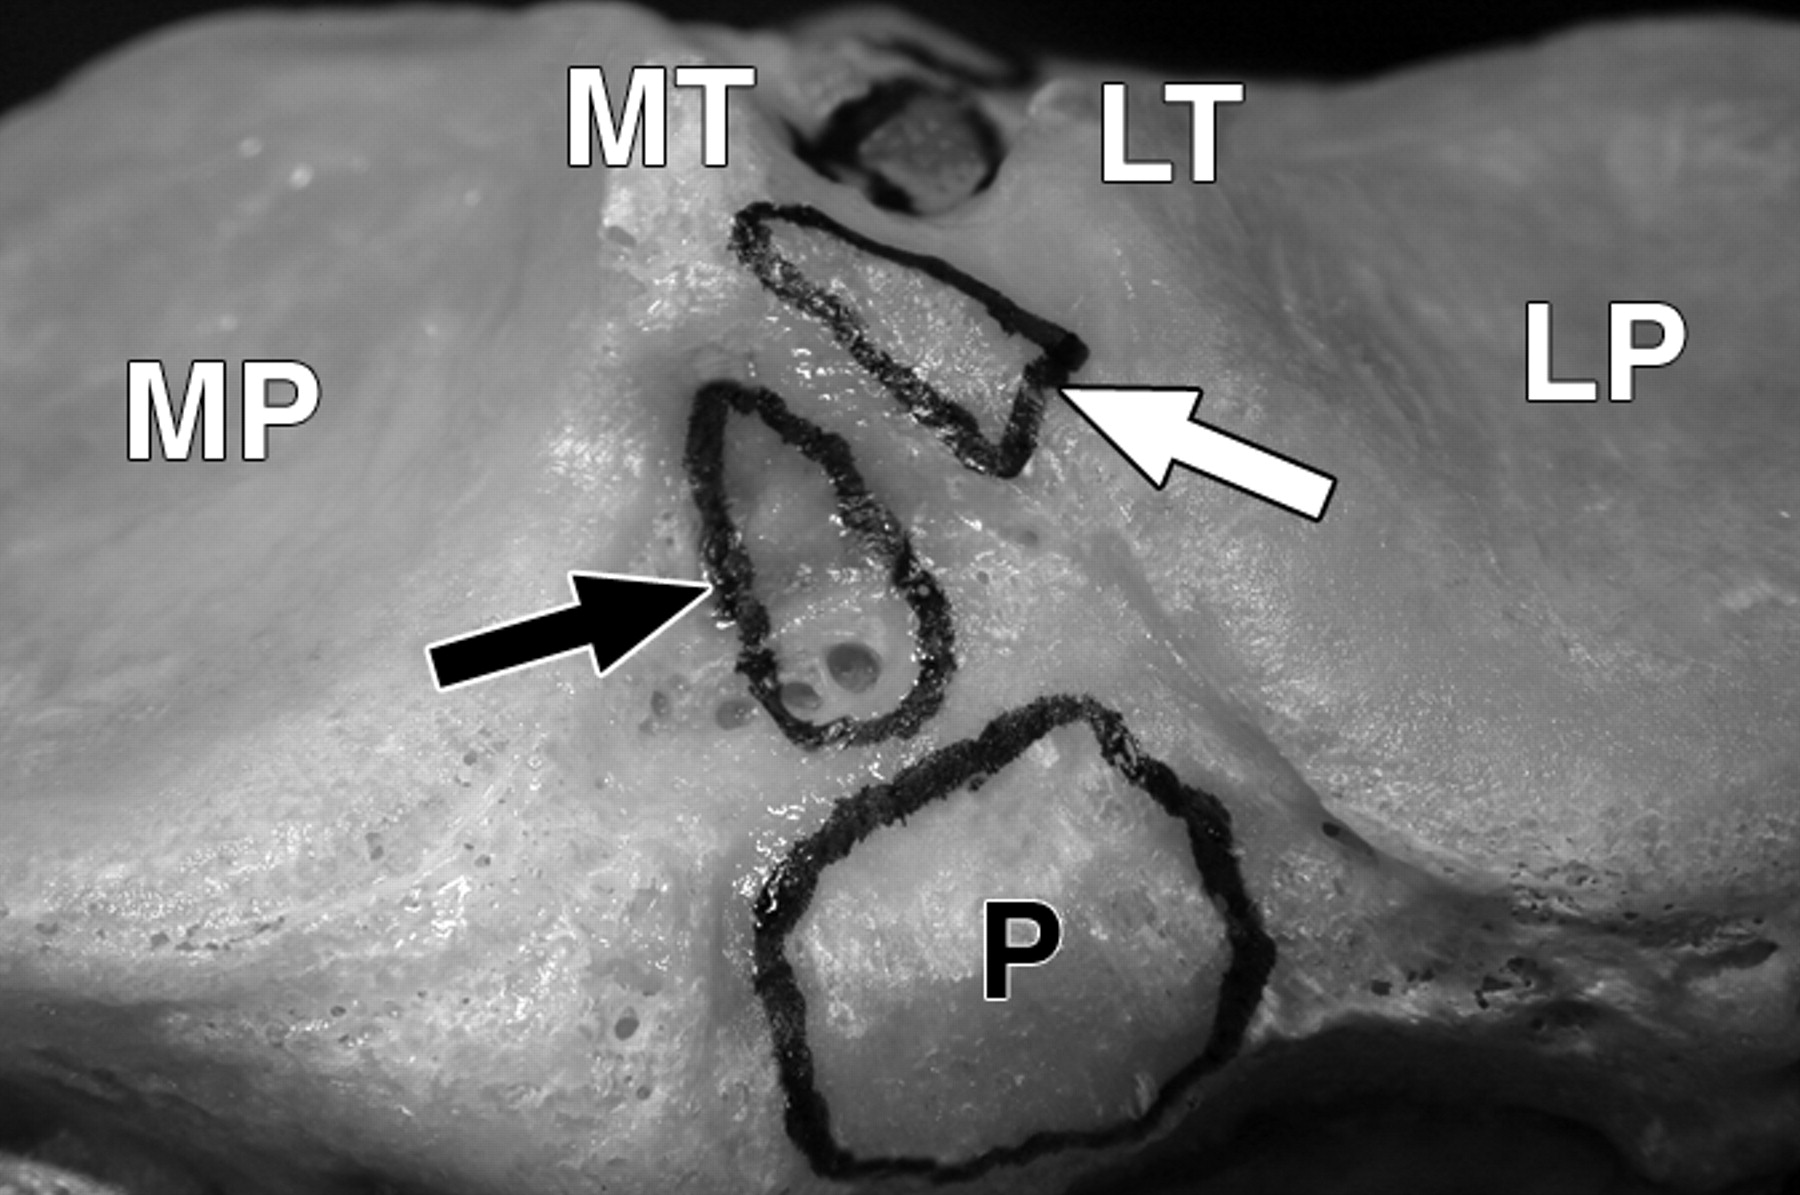

图1C-59岁男性。

黑色长箭头表示内侧半月板(MM)前根;黑色短箭头表示内侧半月板后根;白色长箭头表示外侧半月板(LM)前根;白色短箭头表示外侧半月板后根。侧视图显示了去除软组织结构后胫骨插入部位的相对位置。星号表示前十字韧带。P =后交叉韧带。